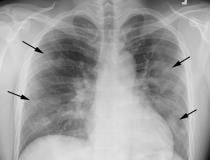

This photo gallery shows the variety of radiological presentations of COVID-19 (SARS-CoV-2) in medical imaging, including computed tomography (CT), radiograph X-rays, ultrasound, echocardiograms and magnetic resonance imaging (MRI). The radiology images show examples of typical COVID pneumonia in the lungs and the numerous complications the virus causes in the body in multiple organs, including the brain, kidneys, heart, abdomen and vascular system.

Ultrasound, especially hand-held ultrasound imaging devices, have become a primary imaging modality for novel coronavirus because of the ease to bag the device and sterilize it after use. CT and mobile X-ray systems are also used as front-line imaging systems for COVID-positive or suspected COVID patients.